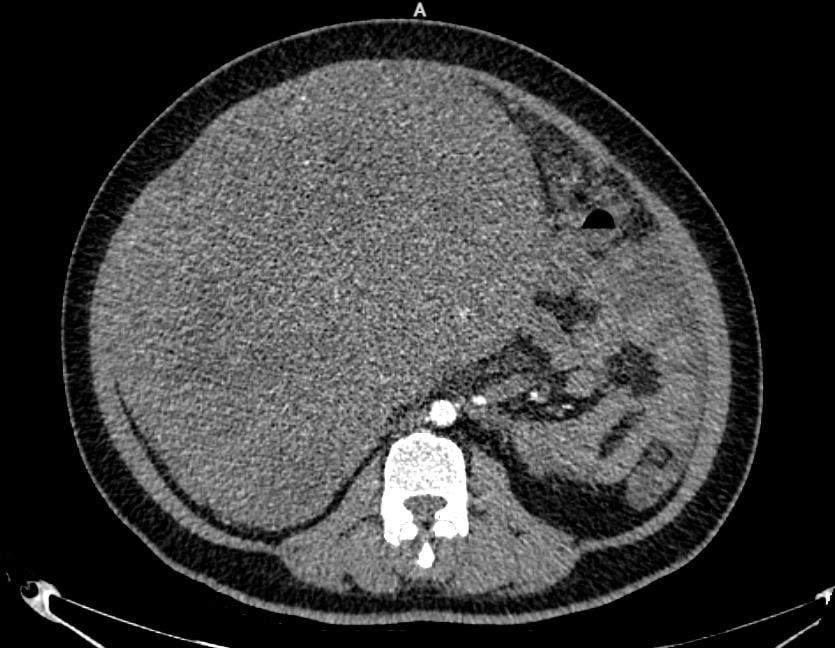

Hình ảnh khối u. Ảnh: BVCC

Kết quả chụp cắt lớp vi tính cho thấy, khối u của bệnh nhân lan tỏa vùng hạ sườn phải, quanh rốn và hạ vị với kích thước lên tới 22,7 x 29cm, bờ không đều. Khối u tiếp xúc và chèn ép nhiều cơ quan như gan, túi mật, thận phải, tụy, đồng thời dính với đáy tử cung. Ngoài ra, bệnh nhân còn có tình trạng dịch ổ bụng nhiều và tràn dịch màng phổi hai bên.